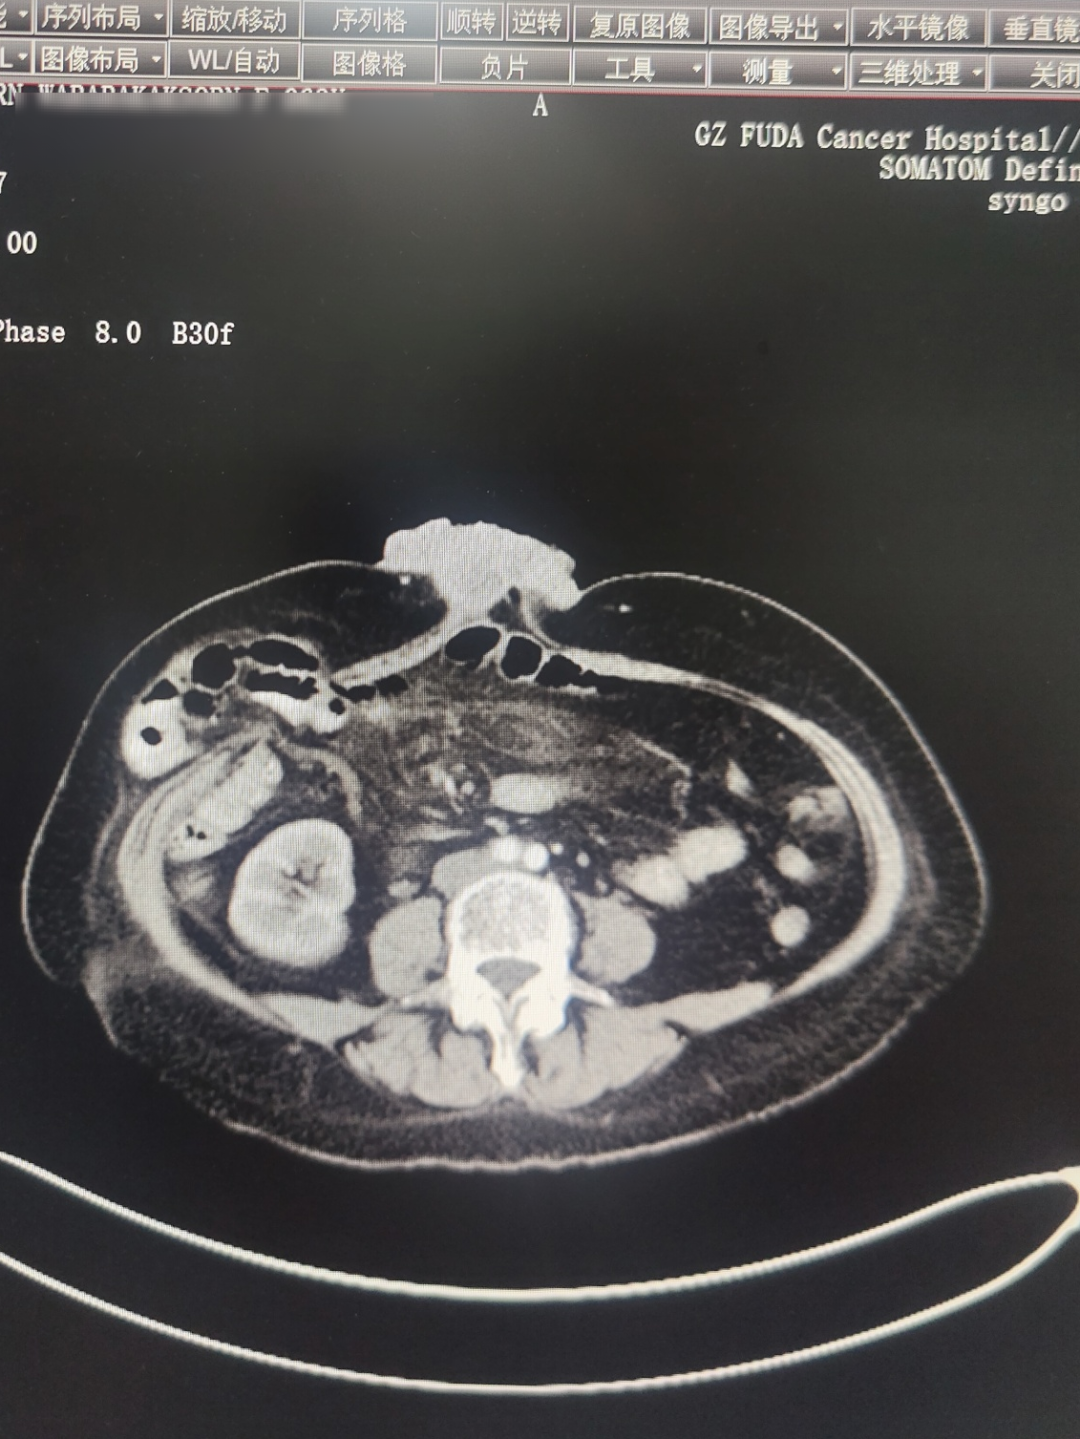

2025年5月影像